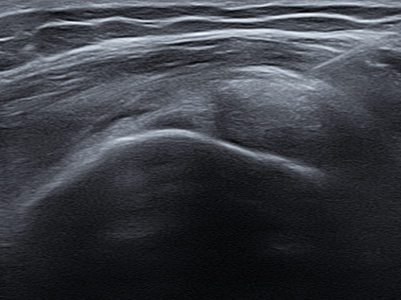

Rotator Cuff Tear

회전근개 파열이란?

회전근개 파열은 ‘회전근개’라고 불리는 어깨관절을 둘러싸고 있는

4개의 힘줄(극상근, 극하근, 소원근, 견갑하근) 중

하나 이상이 파열되는 질환

입니다.

회전근개는 어깨의 안정성을 유지하고, 팔을 들어올리고

회전시키는 동작을 가능하게 하는 중요한 역할을 담당합니다.

어깨 힘줄은 한번 파열되면 자연치유가 어려워

조기 발견과 치료가 중요합니다